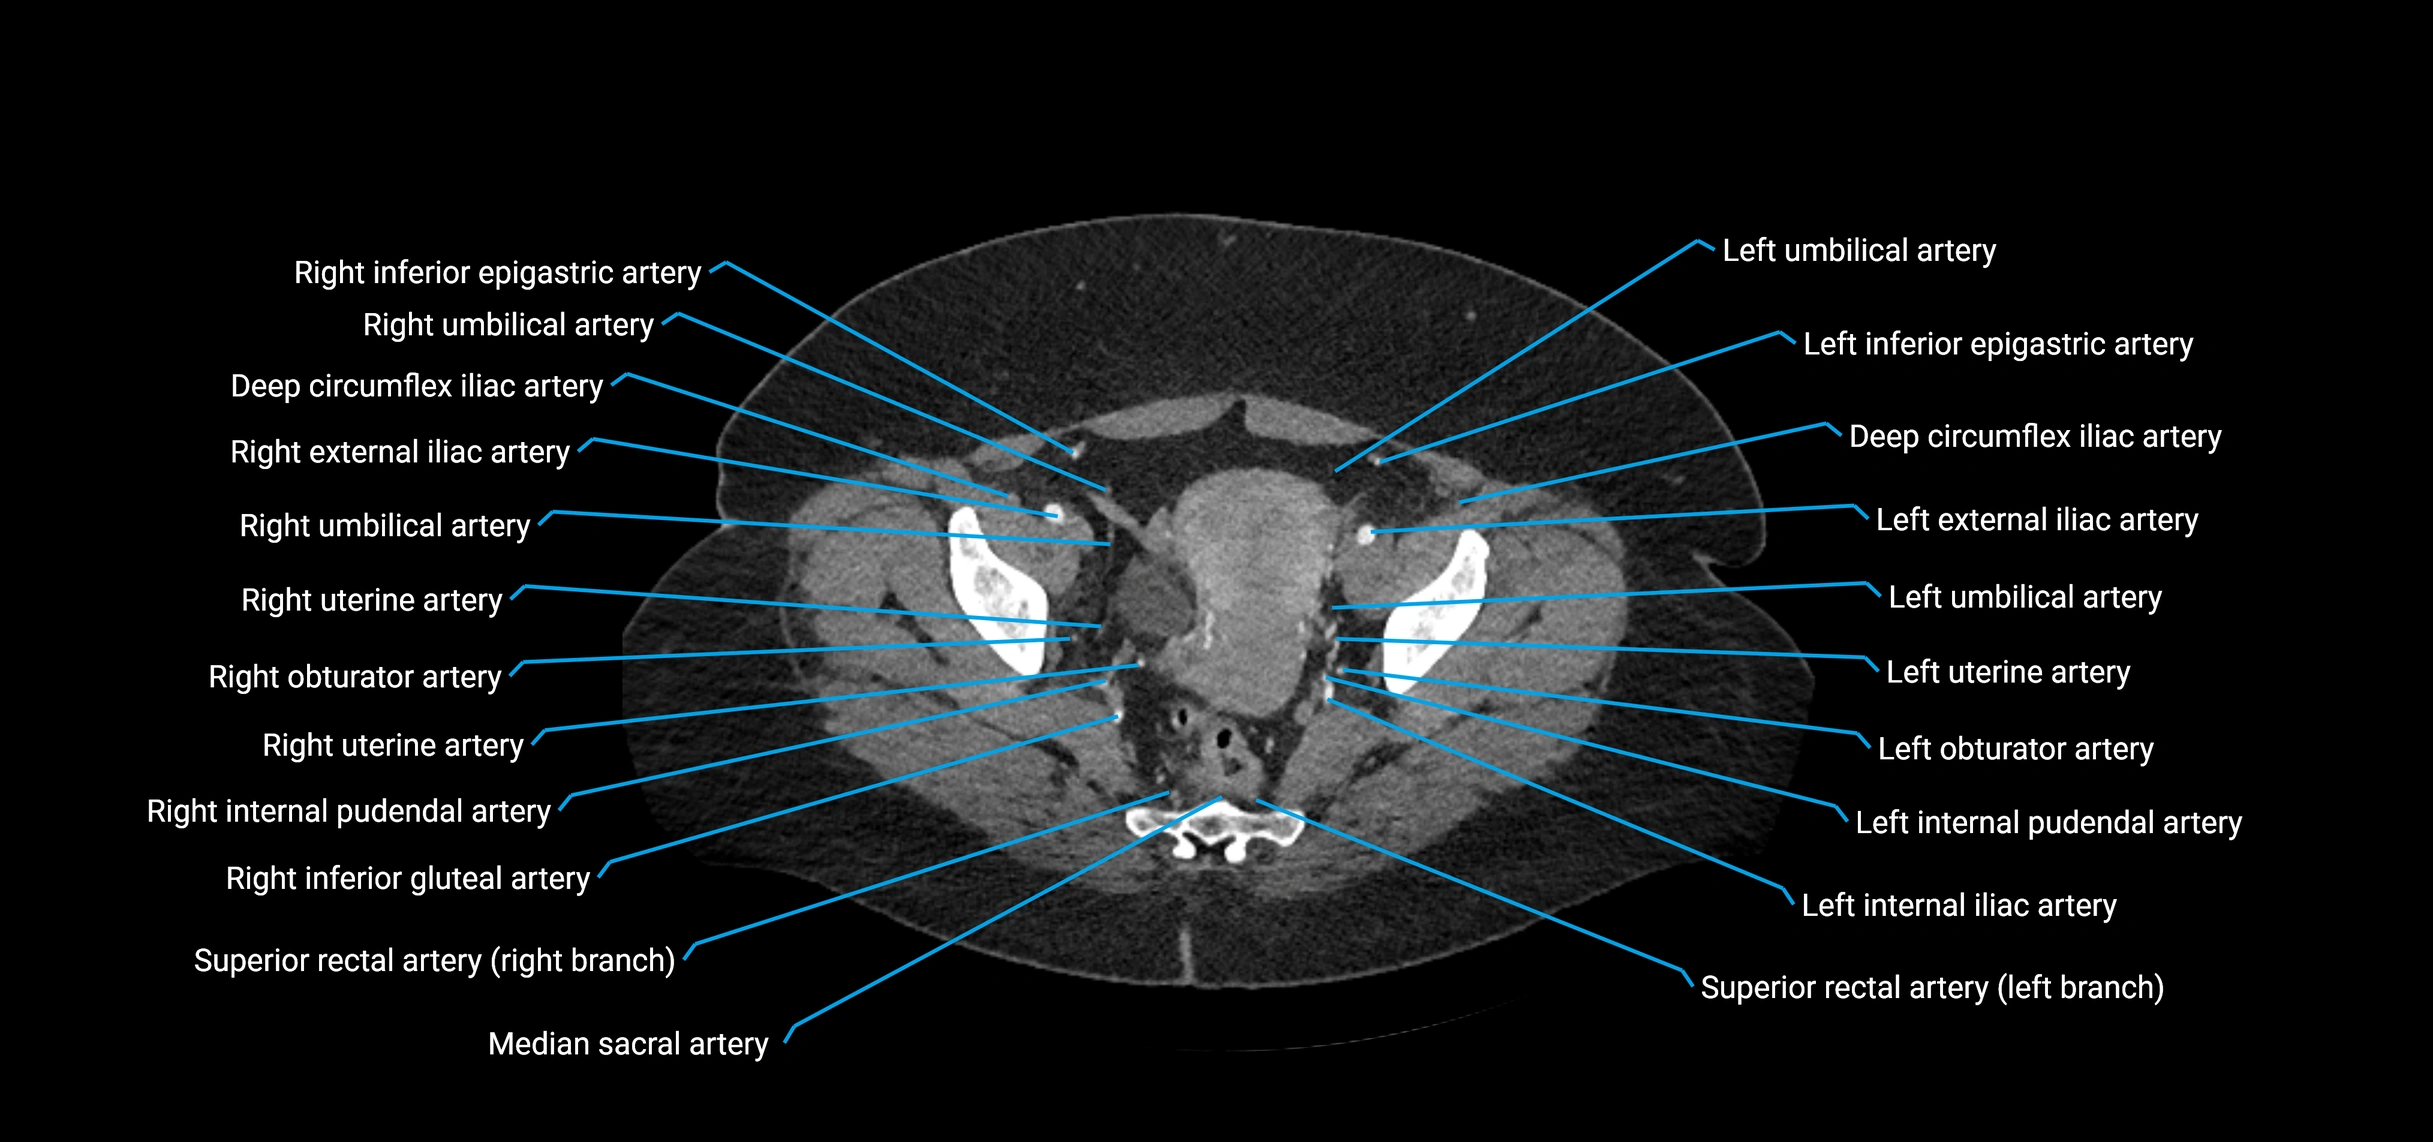

Contrast-enhanced CT (CTA):

• Gold standard for abdominal aortic imaging

• Provides excellent detail of lumen, wall, aneurysm, thrombus, and branch vessels

• Multiplanar and 3D reconstructions help in aneurysm measurement, stent graft planning, and dissection evaluation

• Detects acute rupture, traumatic injury, or occlusion with high sensitivity